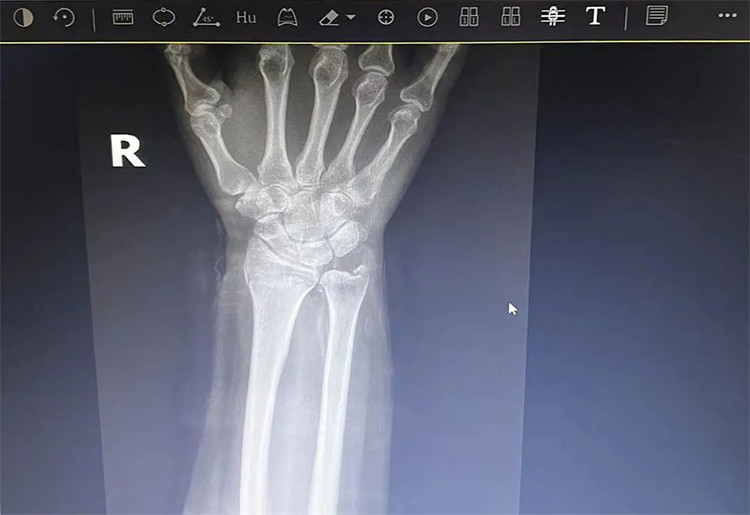

患者老年女性,50多歲,在騎電動(dòng)車(chē)停下時(shí)因電動(dòng)車(chē)倒下,右手著地,當(dāng)即感覺(jué),右腕及骶尾部腫痛伴右關(guān)節(jié)畸形、活動(dòng)受限,急來(lái)我院就診。門(mén)診醫(yī)師結(jié)合病史、查體及輔助檢查后,診斷為:右橈尺骨遠(yuǎn)端骨折、骶尾部挫傷并收入住院部。